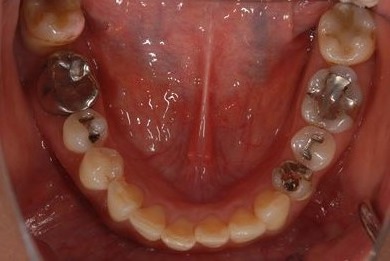

骨再生インプラント治療+セラミック治療+歯肉歯槽骨整形

| 性別/年齢 | 女性 / 42歳 | ||||||||||||||||||||||||||||||||

| 主訴 | インプラント治療を受けたい。 | ||||||||||||||||||||||||||||||||

| 治療方針 | 左上奥欠損部分をインプラント治療にて機能的・審美的回復を行う。 | ||||||||||||||||||||||||||||||||

| 治療内容 | インプラント2本(ソケットリフト)、メタルボンドセラミック3本(メタルボンド用土台1本)、歯肉歯槽骨整形 | ||||||||||||||||||||||||||||||||

| 総治療費 | 1,227,713円 | ||||||||||||||||||||||||||||||||

| 治療期間 | 11ヶ月 |